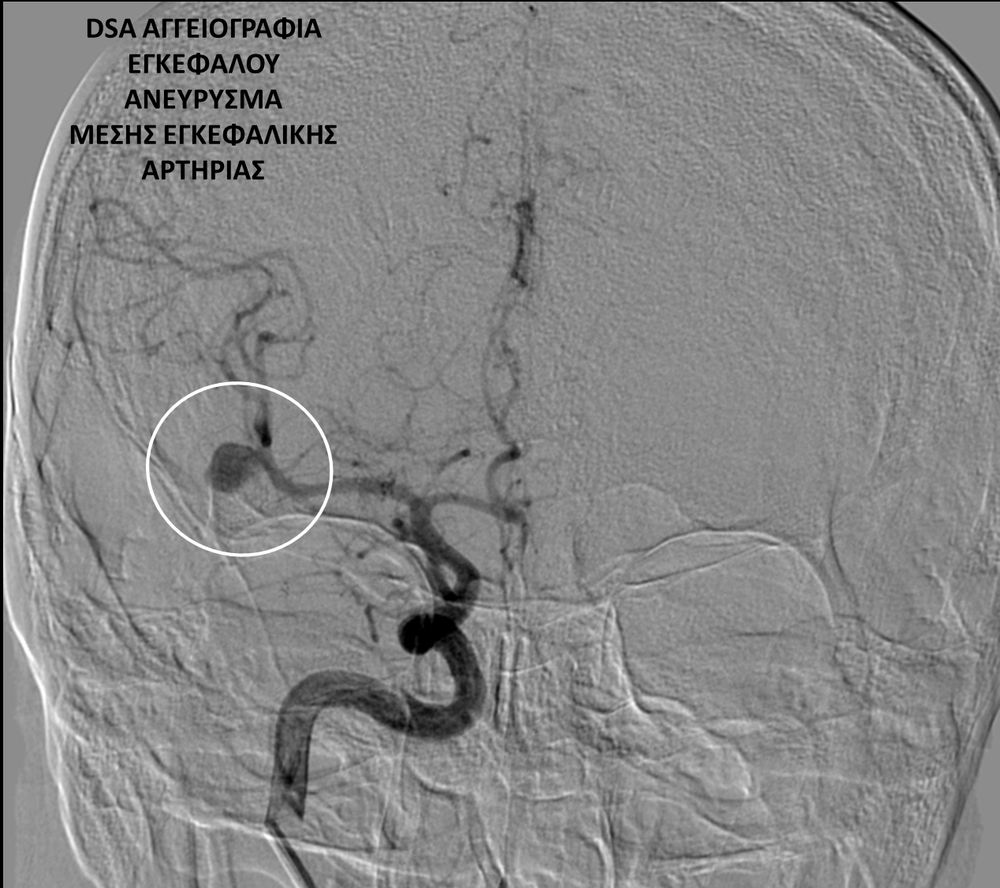

• Η ψηφιακή αγγειογραφία (DSA) αποτελεί την καλύτερη μέθοδο διάγνωσης των αγγειακών παθήσεων.Η αγγειογραφία γίνεται ως εξής: αρχικά παρακεντάται μια αρτηρία πρόσβασης, όπως η μηριαία αρτηρία στη βουβωνική περιοχή ή η βραχιόνια αρτηρία στο βραχίονα. Στη συνέχια προωθείται ένας καθετήρας προς την περιοχή του ενδιαφέροντος και γίνεται η έγχυση σκιαγραφικής ουσίας (σκιαγραφικού) με συνεχή λήψη «εικόνων» των αγγείων-στόχων.